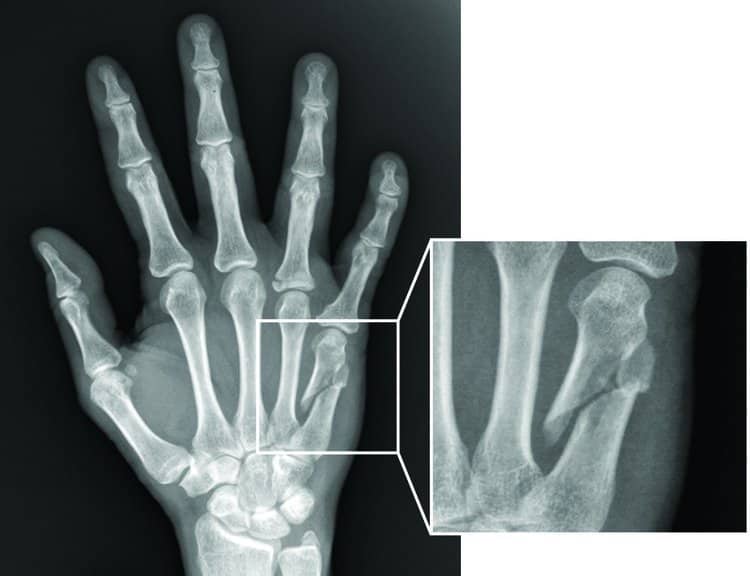

Hỏi bệnh sử và khám thực thể. Chụp X-quang sẽ được thực hiện để xác định chẩn đoán.